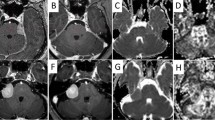

Diffusion-weighted images (DWIs) were acquired in twenty-three patients following surgery, prior chemoradiation and within 7 days following completion of treatment, using b-values ranging from 0 to 5000s/mm2. Mono-exponential diffusion (apparent diffusion coefficient: ADC), isotropic (non-directional) DKI model with apparent diffusivity (Dapp) and kurtosis (Kapp) estimates as well as SE model with distributed-diffusion coefficient (DDC) and mean intra-voxel heterogeneity (α) were computed for all patients prior and after chemoradiation. Median values were calculated for normal appearing white matter (NAWM) and contrast-enhancing tumor (CET). The magnitudes of diffusion change prior and after chemoradiation were used to predict overall survival (OS).

Diffusivity in NAWM was consistent for all diffusion measures during chemoradiation, while diffusivity measurements (ADC, Dapp and DDC) within CET changed significantly. A strong positive correlation existed between ADC, Dapp, and DDC measurements prior to chemoradiation; however, this association was weak following chemoradiation, suggesting a more complex microstructural environment after cytotoxic therapy. When combined with baseline tumor volume and MGMT status, age and ADC changes added significant prognostic values, whereas more complex diffusion models did not show significant value in predicting OS.

Despite increased tissue complexity following chemoradiation, advanced diffusion models have longer acquisition times, provide largely comparable measures of diffusivity, and do not appear to provide additional prognostic value compared to mono-exponential ADC maps.